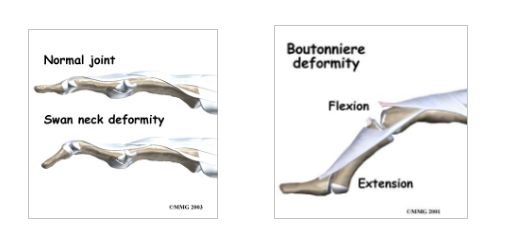

Describe Swan Neck and Boutonnieres

These occur with what?

Tx?

These are with tendon ruptures and lacerations

Swan neck injury is at the DIP joint

Boutonniere injury is at the PIP joint

Refer to ortho